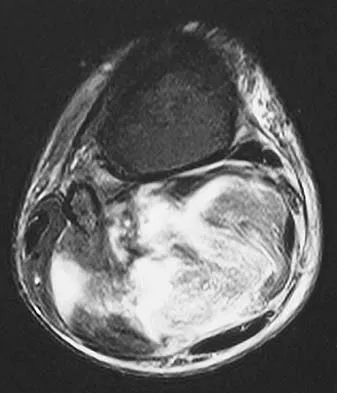

Figures 10a through 10c show the plain radiograph and MRI scans of a 41-year-old man who has right hip pain. What is the most likely diagnosis?

Transient osteoporosis is a self-limited painful but reversible disorder. Although first described in pregnant women, it is more common in young to middle-aged men. The radiograph shows loss of mineralization in the right hip relative to the left side. There is no osseous destruction or cortical expansion typical of metastasis or giant cell tumor. The process is confined to the femoral side of the joint unlike rheumatoid arthritis, which would be centered in the joint. Osteonecrosis is better defined with sharp but irregularly shaped margins, and there is no double-line sign. The MRI scans reveal diffuse edema in the femoral head and neck that is atypical for osteonecrosis. Transient osteoporosis may recur in the same or opposite hip.